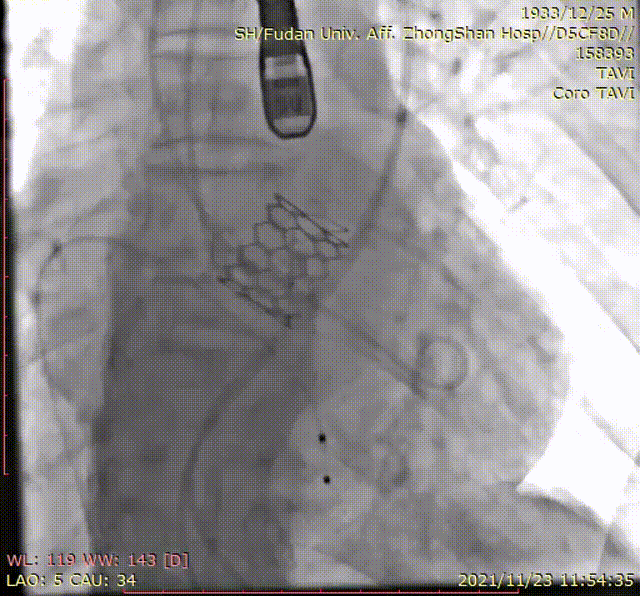

定位环释放

瓣膜精准定位